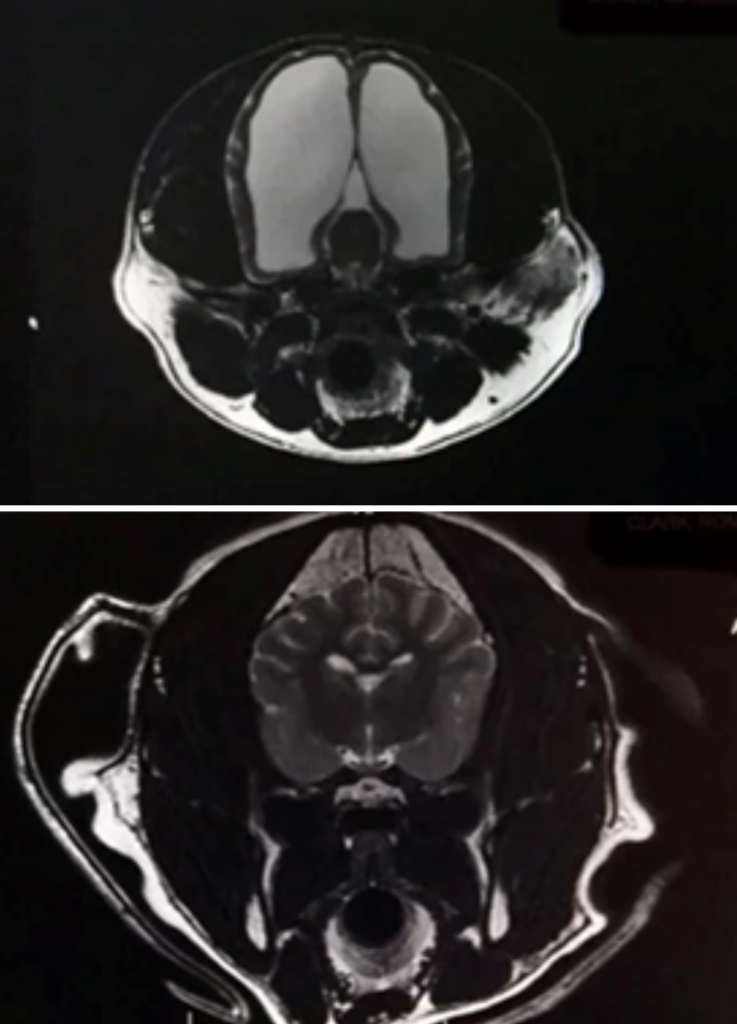

Her story went viral when her owner posted that after adopting her as a “normal” puppy and loving her through everyday dog life, including a litter of puppies, they later learned from an MRI scan that her brain cavity was filled with fluid and only about 5 % of her brain tissue was present.

The dog’s owner shared that she never suspected anything unusual through six happy years, until she had a seizure later in life. A vet visit led to an MRI scan, which shocked everyone: 95 % of her skull was filled with fluid, not brain tissue.

This condition, often related to congenital hydrocephalus in dogs, can sometimes severely impair development, but in her case, she compensated beautifully. Her instinctive behaviours, affection, playfulness, and ability to live comfortably with her family showed that the essence of what makes a dog “a dog” doesn’t always come down to brain volume.